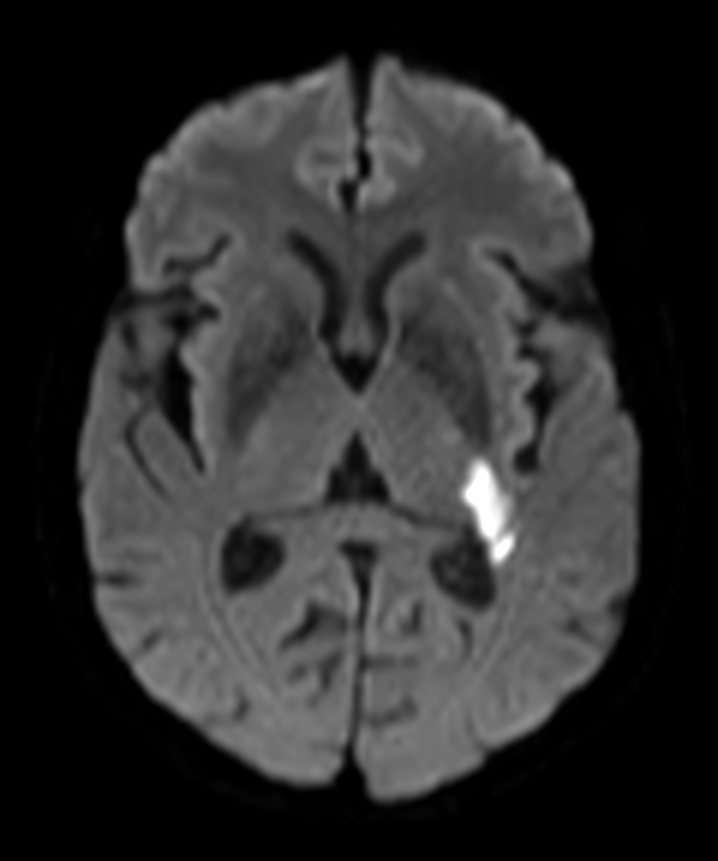

DWI (b1000)

Zoom Diffusion (b1000)